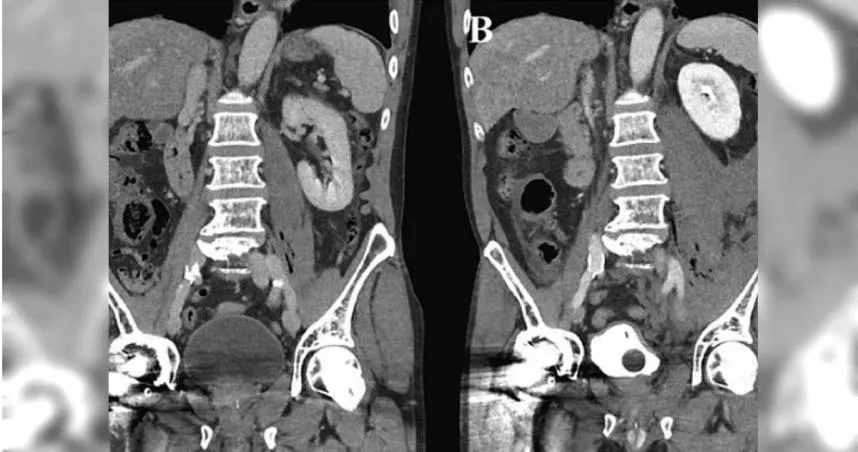

洗腎

換腎

腎臟